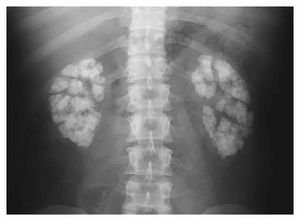

What’s this diagnosis

Primary hyperoxaluria

a lot of Kidney stones

Multiple renal stones